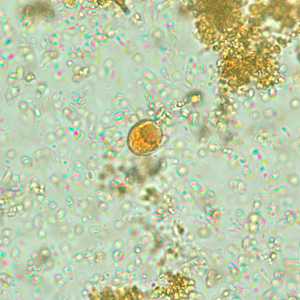

Endolimax nana cysts in concentrated wet mounts.

Figure B: Cyst of E. nana in a direct wet mount stained with iodine.